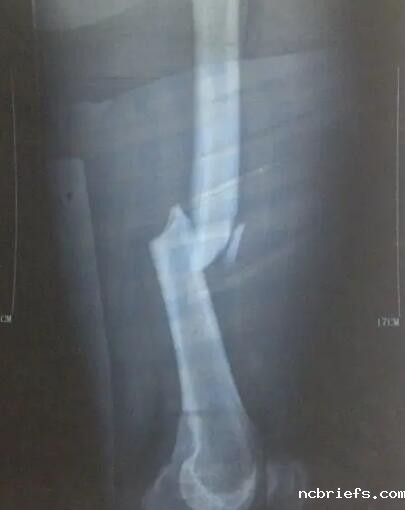

骨密度检测仪厂家提示前几天,有些人说他摔倒了,原本以为没事儿,结论胳膊连续疼了好长时间,去医院做检查,才发现是骨折了。因此大家不要以为骨裂离我们的日常生活很遥远,可能有些人摔个跟斗便会骨裂。那样骨折了应该怎么办?

骨密度检测仪厂家提示骨裂本身就是骨的持续性和完好性遭到毁坏,大部分主要是因为创伤受到暴力行为导致的,病人在骨裂以后,部分会有痛疼、发胀、活动障碍等不适,有的患者状况较为严重,也有有可能出现休克状况,危机生命。

骨密度检测仪厂家提示因此在骨裂以后,大家千万不要托着,觉得自己能撑过去。估且不说骨裂的过程当中带来病人比较大的苦楚,若不及时医治,骨的畸型会引起,后面无法修复,人体基本上均衡会被打破,造成一系列问题。因此发生骨裂,一定要到正规医院积极治疗,那样才会得到立即、妥当的处理方法,防止骨裂伤害进一步加剧。